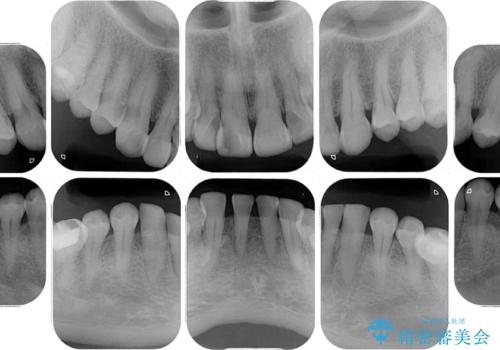

- 前歯の変色や欠損による隙間を気にして来院された患者様です。

上顎前歯は樹脂による変色を覆い隠す処置が行われていましたが、汚れが溜まりやすく厚みも増している状態でした。

上顎前歯は樹脂を外し、下顎前歯の隙間はそれぞれの歯を大きくするように補綴治療を行うことで隙間を埋めることとしました。